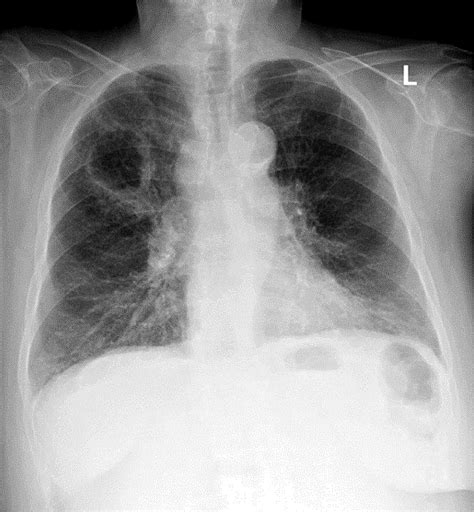

A cavitary lesion of lung is a significant radiological finding that requires careful medical evaluation. In clinical terms, a cavity is defined as a gas-filled space within a pulmonary consolidation, a mass, or a nodule. When a patient undergoes a chest X-ray or a computed tomography (CT) scan and receives this diagnosis, it often triggers immediate concern. However, understanding that these lesions can result from a wide spectrum of causes—ranging from common infections to serious malignancies—is crucial for both patients and healthcare providers to ensure accurate diagnosis and appropriate management.

At its core, a cavitary lesion of lung represents a localized area of the lung parenchyma that has been destroyed or excavated. This destruction often occurs when an area of diseased lung tissue undergoes necrosis—the death of cells—and the necrotic material is subsequently evacuated, usually through the bronchial tree. This leaves behind a hollow, air-filled void that appears distinctly on medical imaging.

When a physician identifies a cavitary lesion of lung on imaging, they will typically initiate a systematic investigation to determine the etiology. The process often involves a blend of history taking, physical examination, laboratory testing, and advanced imaging or biopsy.

Distinguishing Features on Imaging

Radiologists look for specific markers to help narrow down the diagnosis. The appearance of the cavity's wall, for instance, provides vital clues: